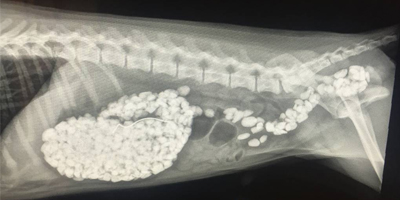

Data reveals highest cost drivers for cats and dogsJanuary 22, 2019Vomiting and/or diarrhea and the ingestion of foreign objects are among the top cost drivers of veterinary care for dogs and cats.